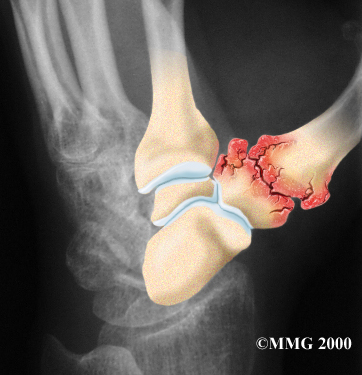

Degenerative Arthritis

Injury to a joint, such as a bad sprain or fracture, can cause damage to the articular cartilage. An injury to the CMC joint of the thumb, even if it does not injure the articular cartilage directly, can alter how the joint works. After a fracture of the thumb metacarpal, the bone fragments may heal in slightly different positions. The joints may then line up differently. This is also true when the ligaments around the CMC joint are damaged by a sprain. When an injury results in a change in the way the joint moves, the injury may increase the forces on the articular cartilage surfaces. This is similar to any mechanical device or machinery. If the mechanism is out of balance, it tends to wear out faster.

Over many years this imbalance in the joint mechanics can lead to damage on the articular surface. Since articular cartilage cannot heal itself very well, the damage adds up. Eventually, the joint is no longer able to compensate for the increasing damage, and it begins to hurt. Damage has occurred well before the pain begins.

Your doctor may take X-rays to see how much the joint is damaged.

X-Rays

This test usually determines how bad the degenerative arthritis has become. How much articular cartilage remains in the joint can be estimated with the X-rays.